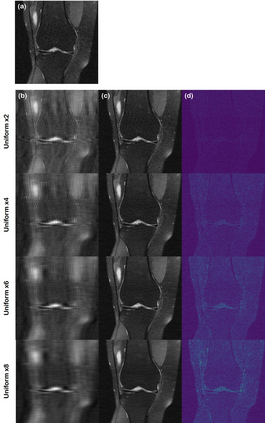

Score-based diffusion models provide a powerful way to model images using the gradient of the data distribution. Leveraging the learned score function as a prior, here we introduce a way to sample data from a conditional distribution given the measurements, such that the model can be readily used for solving inverse problems in imaging, especially for accelerated MRI. In short, we train a continuous time-dependent score function with denoising score matching. Then, at the inference stage, we iterate between numerical SDE solver and data consistency projection step to achieve reconstruction. Our model requires magnitude images only for training, and yet is able to reconstruct complex-valued data, and even extends to parallel imaging. The proposed method is agnostic to sub-sampling patterns, and can be used with any sampling schemes. Also, due to its generative nature, our approach can quantify uncertainty, which is not possible with standard regression settings. On top of all the advantages, our method also has very strong performance, even beating the models trained with full supervision. With extensive experiments, we verify the superiority of our method in terms of quality and practicality.